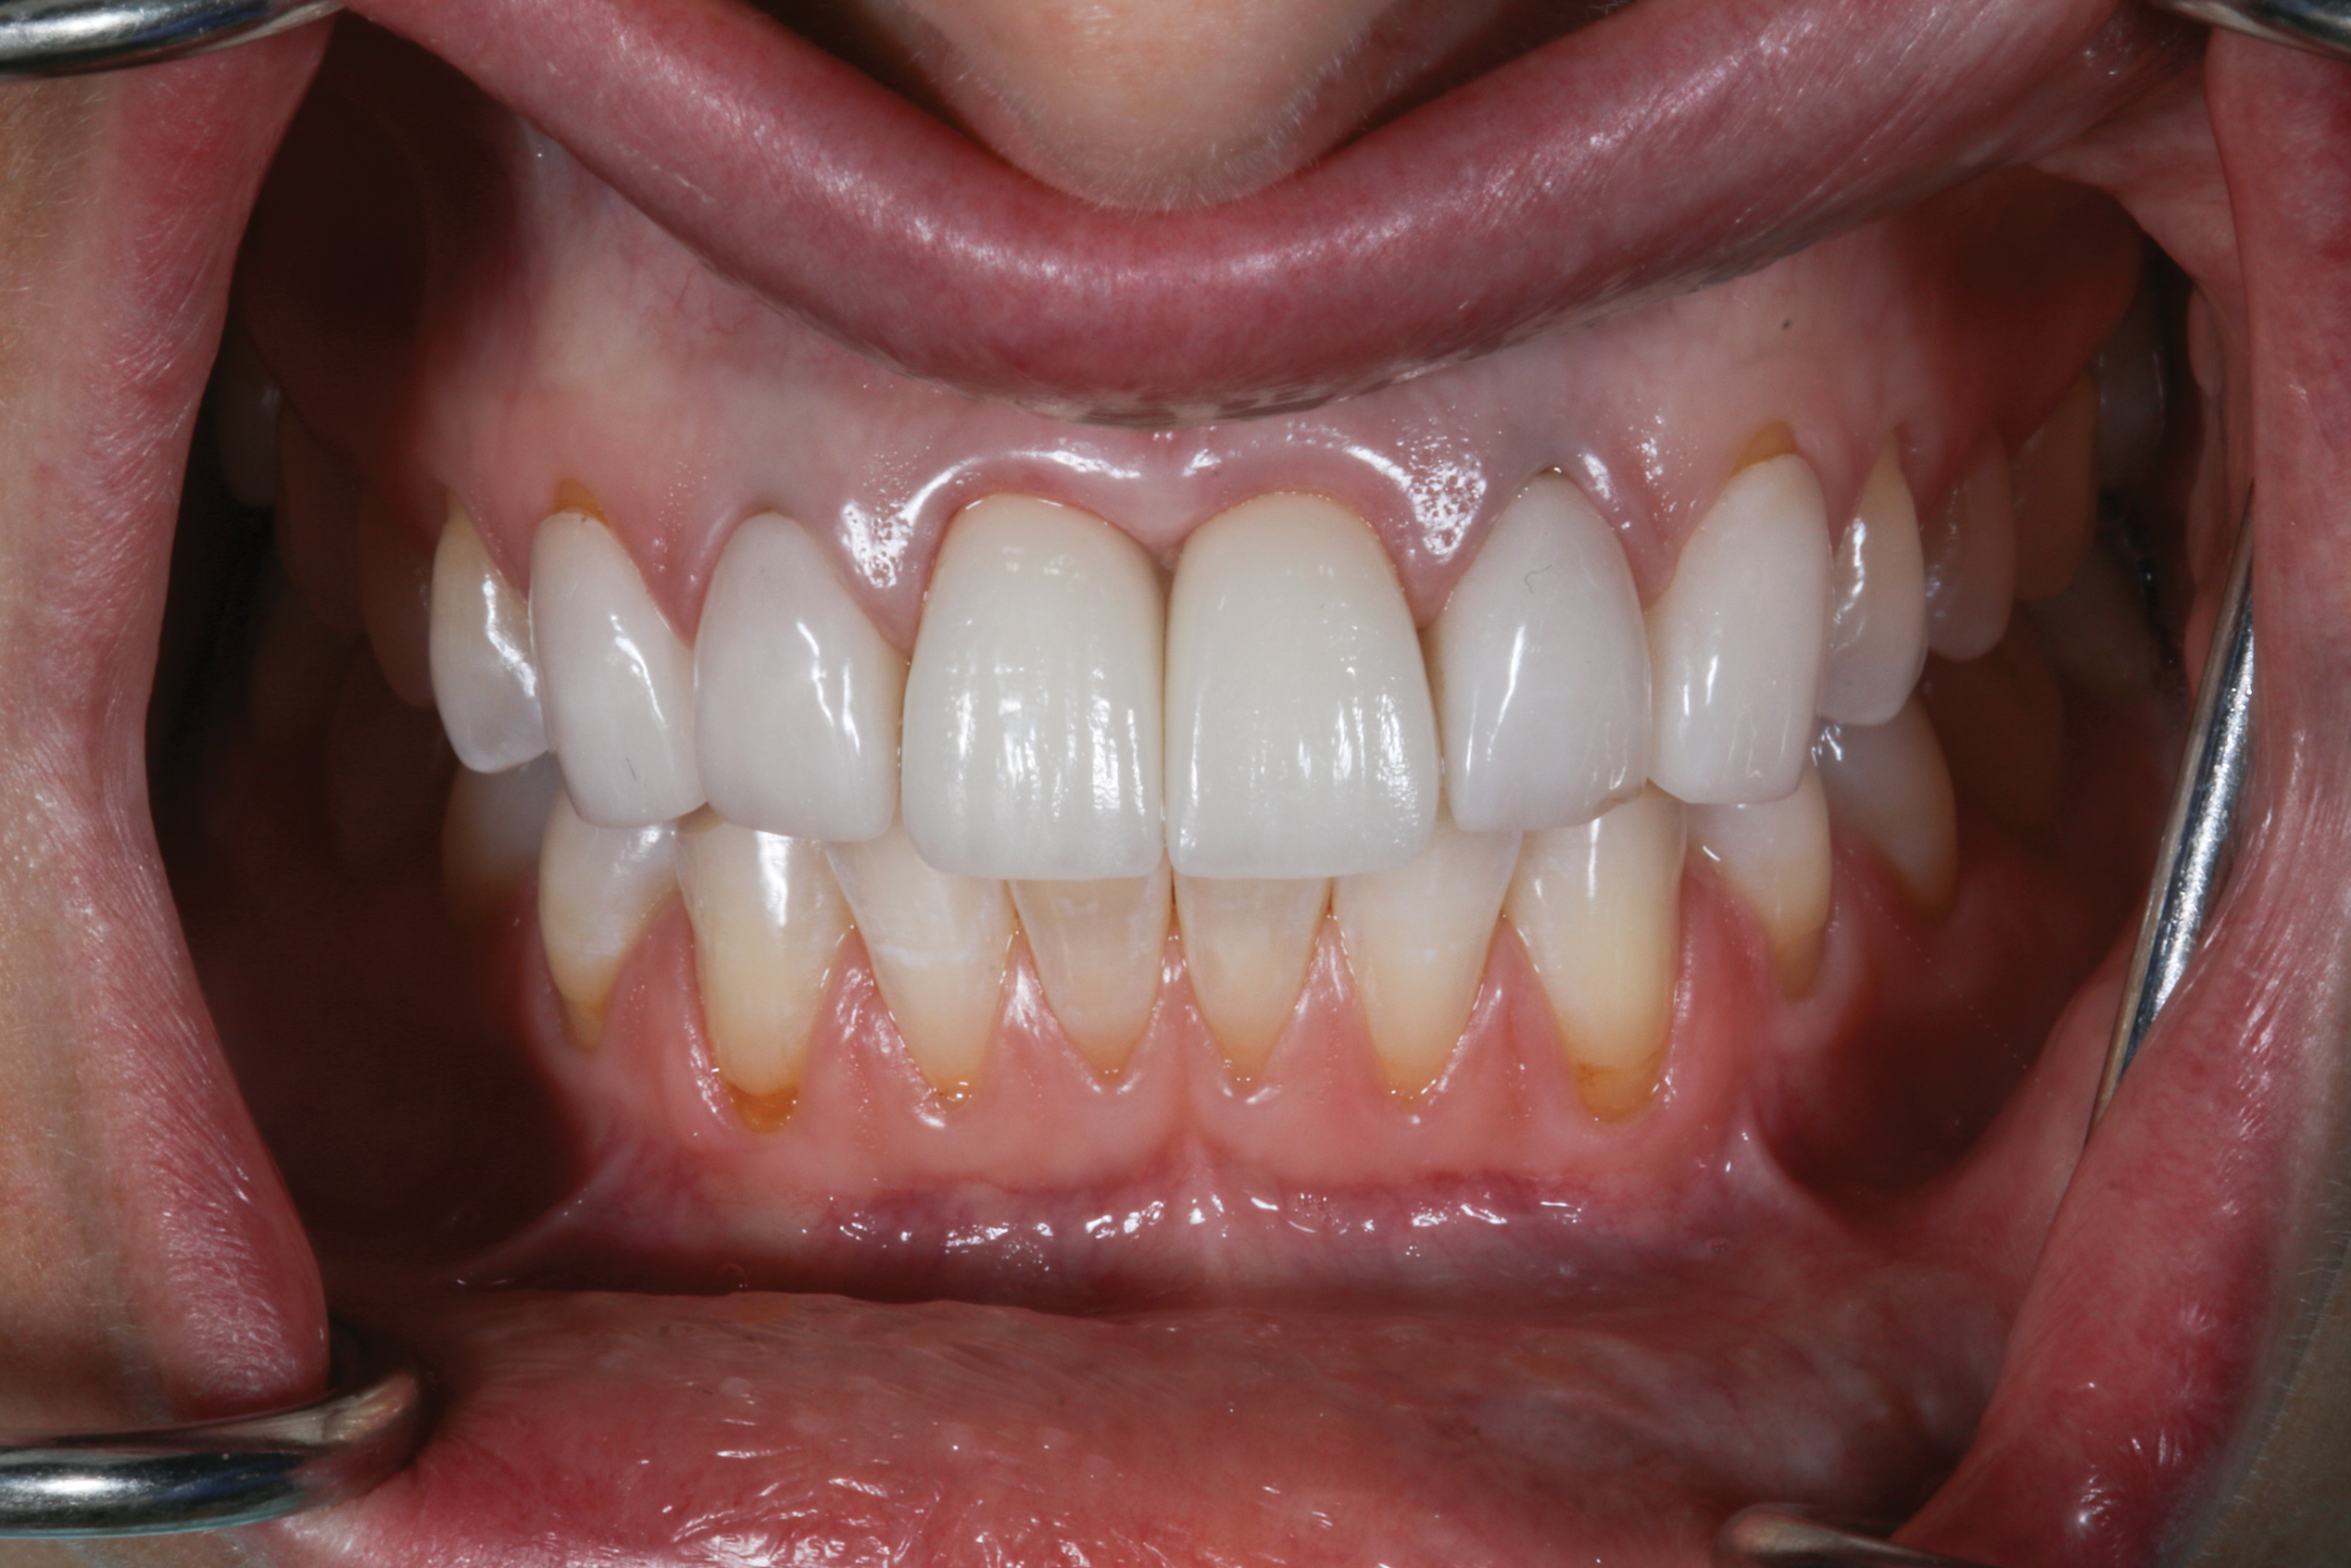

At 3 months, osseointegration was confirmed and screw-retained provisionals were used for soft-tissue grooming. Final prosthetic phase completion occurred at 6 months (Figure 12).

Fig 12. Final prosthetic outcome.

Figure 12